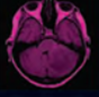

Su forma de presentación en imágenes es muy típica, como una lesión de tamaño variable, con necrosis central, focos de hemorragia y un comportamiento agresivo loco-regional.

Glioblastoma afecta predominantemente los hemisferios cerebrales, siendo muy poco frecuente en fosa posterior, sobre todo en el cerebelo. A pesar de esto existen cada vez más casos reportados en fosa posterior, por lo que entendemos de gran interés analizar su forma de presentación y los elementos que permiten sospechar el diagnóstico previo a la cirugía.

Es objetivo de este trabajo analizar la forma de presentación de los glioblastomas localizados en el cerebelo y sus características en resonancia magnética a partir de una serie de casos que se presentaron en nuestro centro.